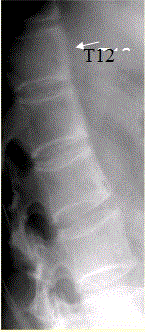

问题 患者男,35岁,外伤后行腰椎CR检查,结果如下图。 观察所给出的CT图像(下图),你的判断是

选项 A.右侧椎肋关节面骨侵蚀 B.椎体前缘骨炎 C.椎体前缘仅仅表现为轻度骨质增生 D.骶髂关节未见异常改变 E.骶髂关节面毛糙 F.骶髂关节间隙模糊

答案 ABEF